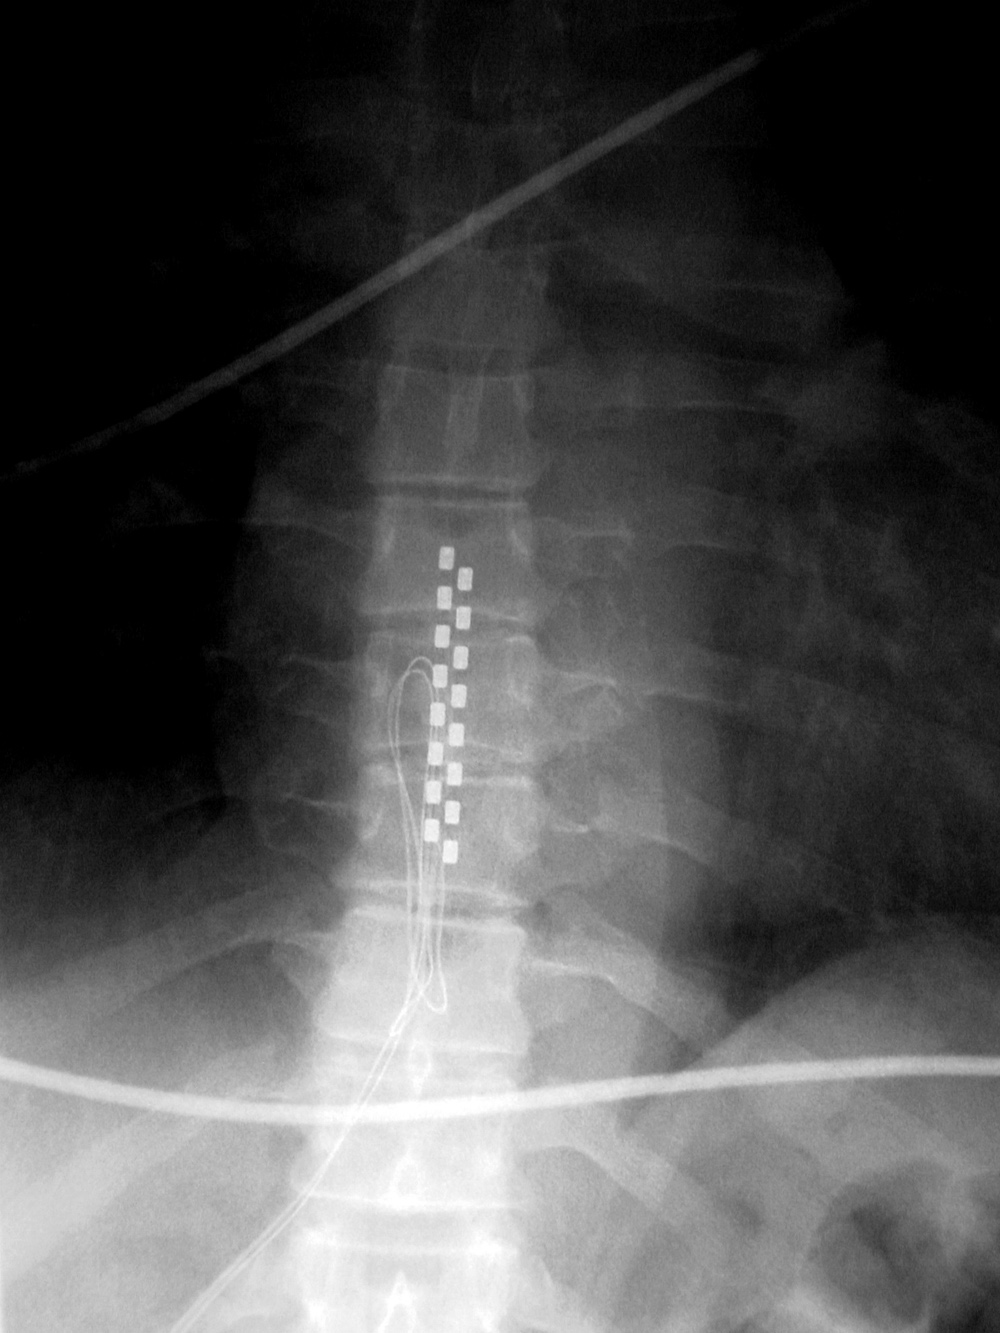

| Zero-Profile lumbar fixation L2-L5 |

|

| 45 year-old woman with L2-5 anterior lumbar interbody fusion (ALIF) for low back pain. The lateral views are respectively in neutral and flexion positions. The CT images are selected slices in the coronal and sagittal planes, respectively. |

| Zero-Profile lumbar fixation L2-L4 |

| 45 year-old woman with L2-5 anterior lumbar interbody fusion (ALIF) for low back pain. |

Anterior lumbar interbody fusion (ALIF) has become more popular and is a somewhat limited procedure (figure: ALIF; figure: zero-profile lumbar fixation L2-5). It offers an easy approach to the anterior disk space without opening the spinal canal or neural foramina, such as the case with posterior lumbar interbody fusion (PLIF) or transforaminal lumbar interbody fusion (TLIF). ALIF allows the placement of a large interbody fusion device and easy and complete diskectomy (Mobbs, 2013). ALIF is used for chronic back pain of discogenic origin over 1 - 3 levels.

ALIF is often performed with zero-profile systems using a low profile spacer anchored by fixation screws into vertebral bodies above and below the diskectomy level (figure: zero-profile lumbar fixation L2-5). The native disks are usually replaced with PEEK artificial disks. While ALIF is somewhat of a more limited surgery compared to several other approaches, it has the disadvantage of potential vascular or bowel injury resulting from the anterior approach to the spine. There has to be mobilization of the great blood vessels and peritoneal contents away from the spine exposing them to possible injury (Mobbs, 2013).